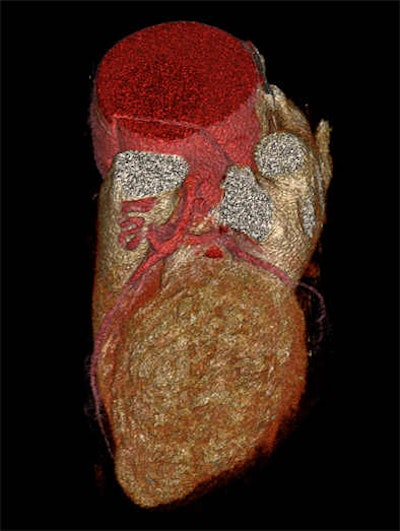

Images of the whole aorta were acquired using a wide-volume protocol; each volume was scanned in a single heartbeat with 16-cm anatomic coverage. The second volume was positioned to cover the whole heart to ensure that all the segments of coronary arteries were in the same dataset. The table is stationary during each acquisition, and then moves to the next location for the next CT data acquisition. Patient is a 23-year-old woman with Marfan syndrome combined with coronary-pulmonary fistula, and a Stanford type A aortic dissection. All images courtesy of Dr. Yu Li.

Images were postprocessed on a workstation (Vitrea FX Workstation, Vital) by an experienced technologist who created 1-mm-thick axial and multiplanar reformations as well as volume-rendered and maximum-intensity projection images of the aorta. Multiplanar reconstructions of the angiographic view also were created for analysis of the coronary arteries. The images were reviewed by two experienced cardiac radiologists who were blinded to patients' clinical information.

CTA of the aorta is a common imaging technique due to its speed and resolution, according to the researchers. But motion in the ascending aorta can be a problem without ECG gating. Using 320-detector-row CT, image quality is acceptable throughout, and for Stanford type A aortic dissection, CTA showed the relationship between the intimal flap, and the aortic valve and the coronary ostium "without obvious motion artifacts," they stated.